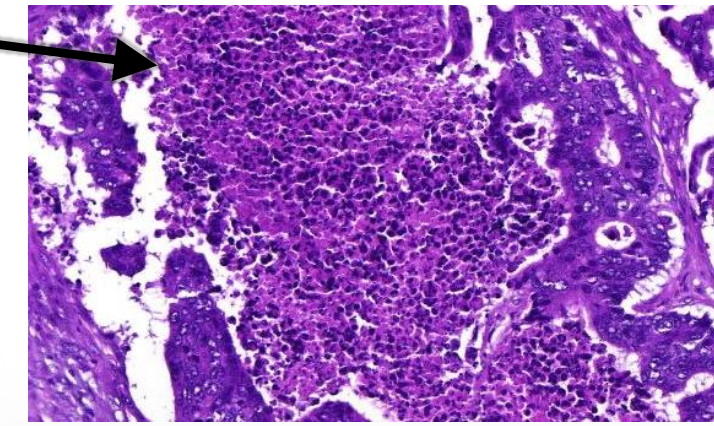

pathologische kenmerken multiple myeloom

mature en abnormale plasmacellen

hypercellulair

anisocytose

nucleoli duidelijk aanwezig

megakaryocyten

voorlopercellen van granulocyten en erythrocyten

vetcellen

osteocytes

multiple myeloom